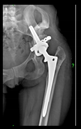

The radiological examination allowed us to verify the close bone-to-implant contact and the unchanged position of the implant during follow-up.

In all the cases operated with the above-described targeting procedure, the stems of the cups remained between the cortical bone surfaces without perforation of the linea terminalis, as shown by postoperative radiographs. There were no complicated surgical situations. In 16 cases, the wound healings were uneventful, and the hips were able to bear weight again after postoperative rehabilitation.